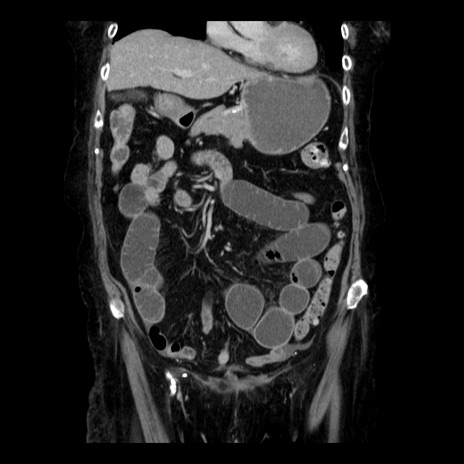

症例14(冠状断像)

【症例】 90歳代女性

【主訴】 腹痛・嘔吐

【現病歴】今朝から左側腹部痛を認めた。 経過観察していたが、嘔吐を認めたため来院。

【既往歴】 子宮癌術後

【身体所見】 意識清明、BP 127/54mmHg、P 98bpm Sp02 95%(RA)、BT 35.8°C、腹部平坦・軟腸ぜん動音聴取良好、右下腹部圧痛(+) 反跳痛なし

【データ】WBC 9800、CRP 0.46